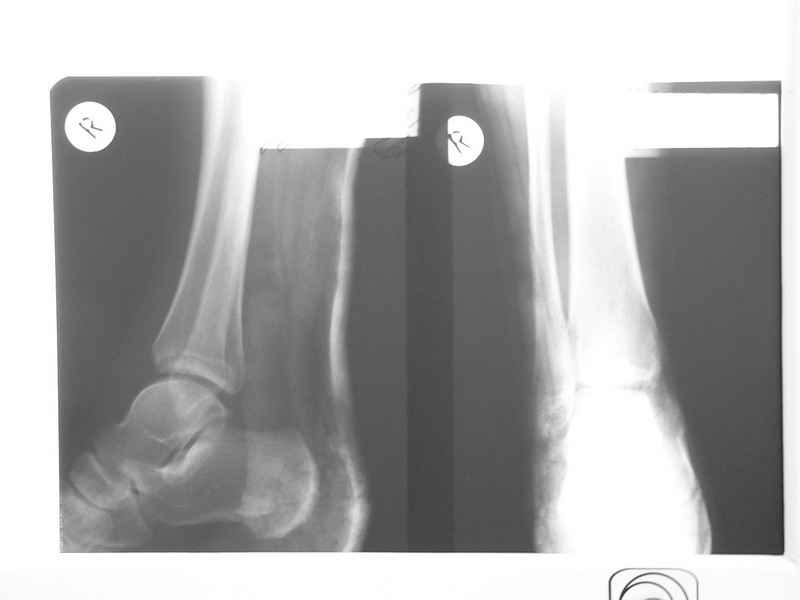

Уважаемые коллеги! Прошу прощения за собственную невнимательность. У больной травма не 1 января 2011г., а 1 декабря 2010г., т.е. уже 2 месяца.

Прилагаю данные фистулогрфии. Основной вопрос, все же, лечить консервативно или оперативно? Если оперативно, то какой объем? А что если прийдеться резецировать всю медиальную лодыжку!?

С уважением Александр Белоконь!